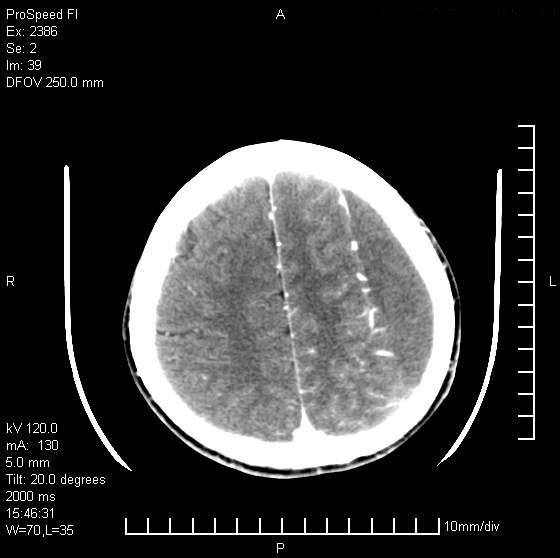

以下是引用天南地北在2007-9-19 18:43:00的发言:[br]典型慢性硬膜外血肿[br][br][本贴已被 天南地北 于 2007-9-19 18:44:11 修改过]

以下是引用曼一拍在2007-9-20 11:06:00的发言:[br]支持慢性硬膜下血肿.[br]慢性硬膜下积液:血肿有包膜,ct值稍高于脑脊液,增强可有染色。不典型者血肿可多呈梭形.是硬脑膜与蛛网膜之间的潜在腔隙内的血肿。[br]鉴别:[br]1\\硬膜外血肿:是颅脑外伤后脑膜或板障内血管破裂,血液在颅骨与硬膜之间积聚所致.通常是脑膜动脉破裂,也可因静脉窦破裂或颅骨的板障静脉出血,发生于外伤的着力部,常与颅骨骨折并存。脑膜动脉出血则急,若是板障静脉出血在则可有慢性。[br]2\\硬膜下积液:(硬膜下水瘤)[br]是由于蛛网膜破裂,脑脊液经蛛网膜破口进入硬膜下腔不能回流。或水肿阻塞而形成。[br]ct表现:颅骨内板下方新月形低密度区近似脑脊液密度;占位效应清,周围无脑水肿。[br]